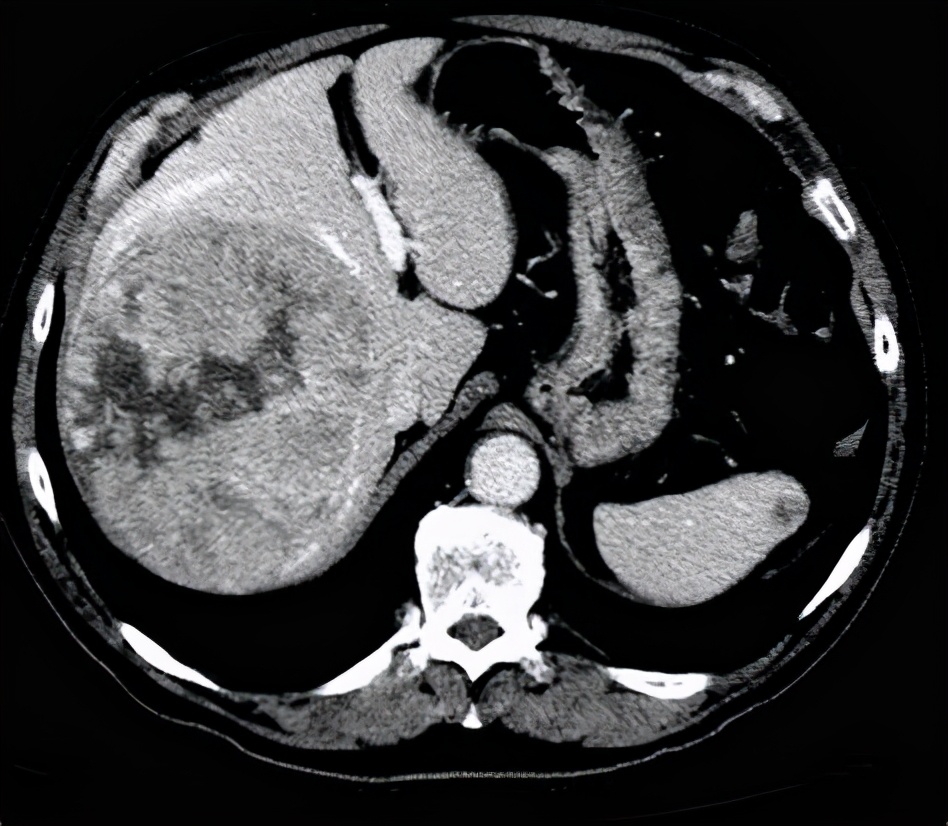

其实肝脏在肚子的右上方,肺脏下面就是肝脏了。

真不清楚的也可以看看图片,大概就是这样的位置,临床中称为右上腹,也就是肝脏的区域。